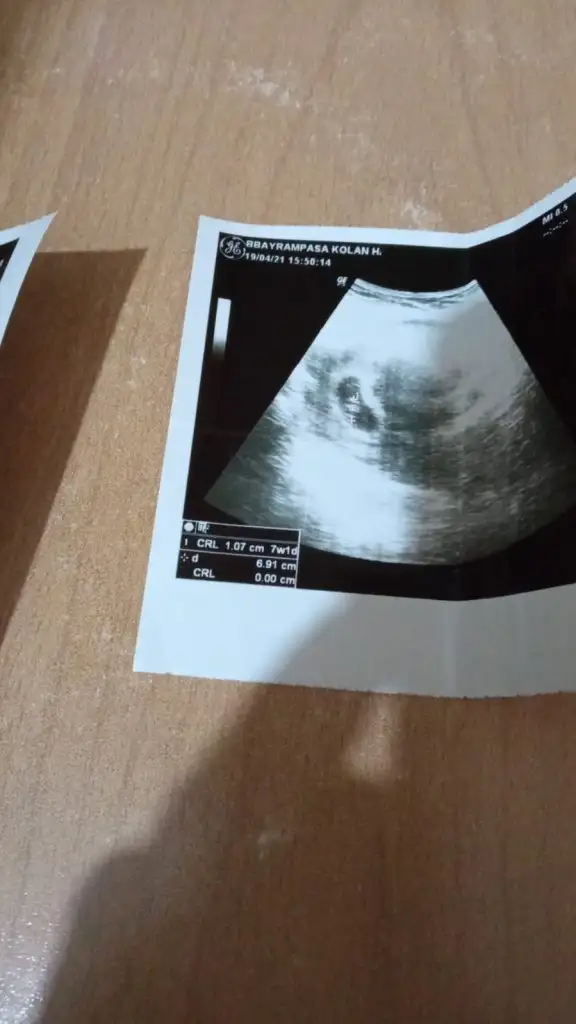

☺️8+3

• Screenshot_2021-04-18-21-49-43-122_com.miui.gallery.webp

Screenshot_2021-04-18-21-49-43-122_com.miui.gallery.webp

15,8 KB · Görüntüleme: 71